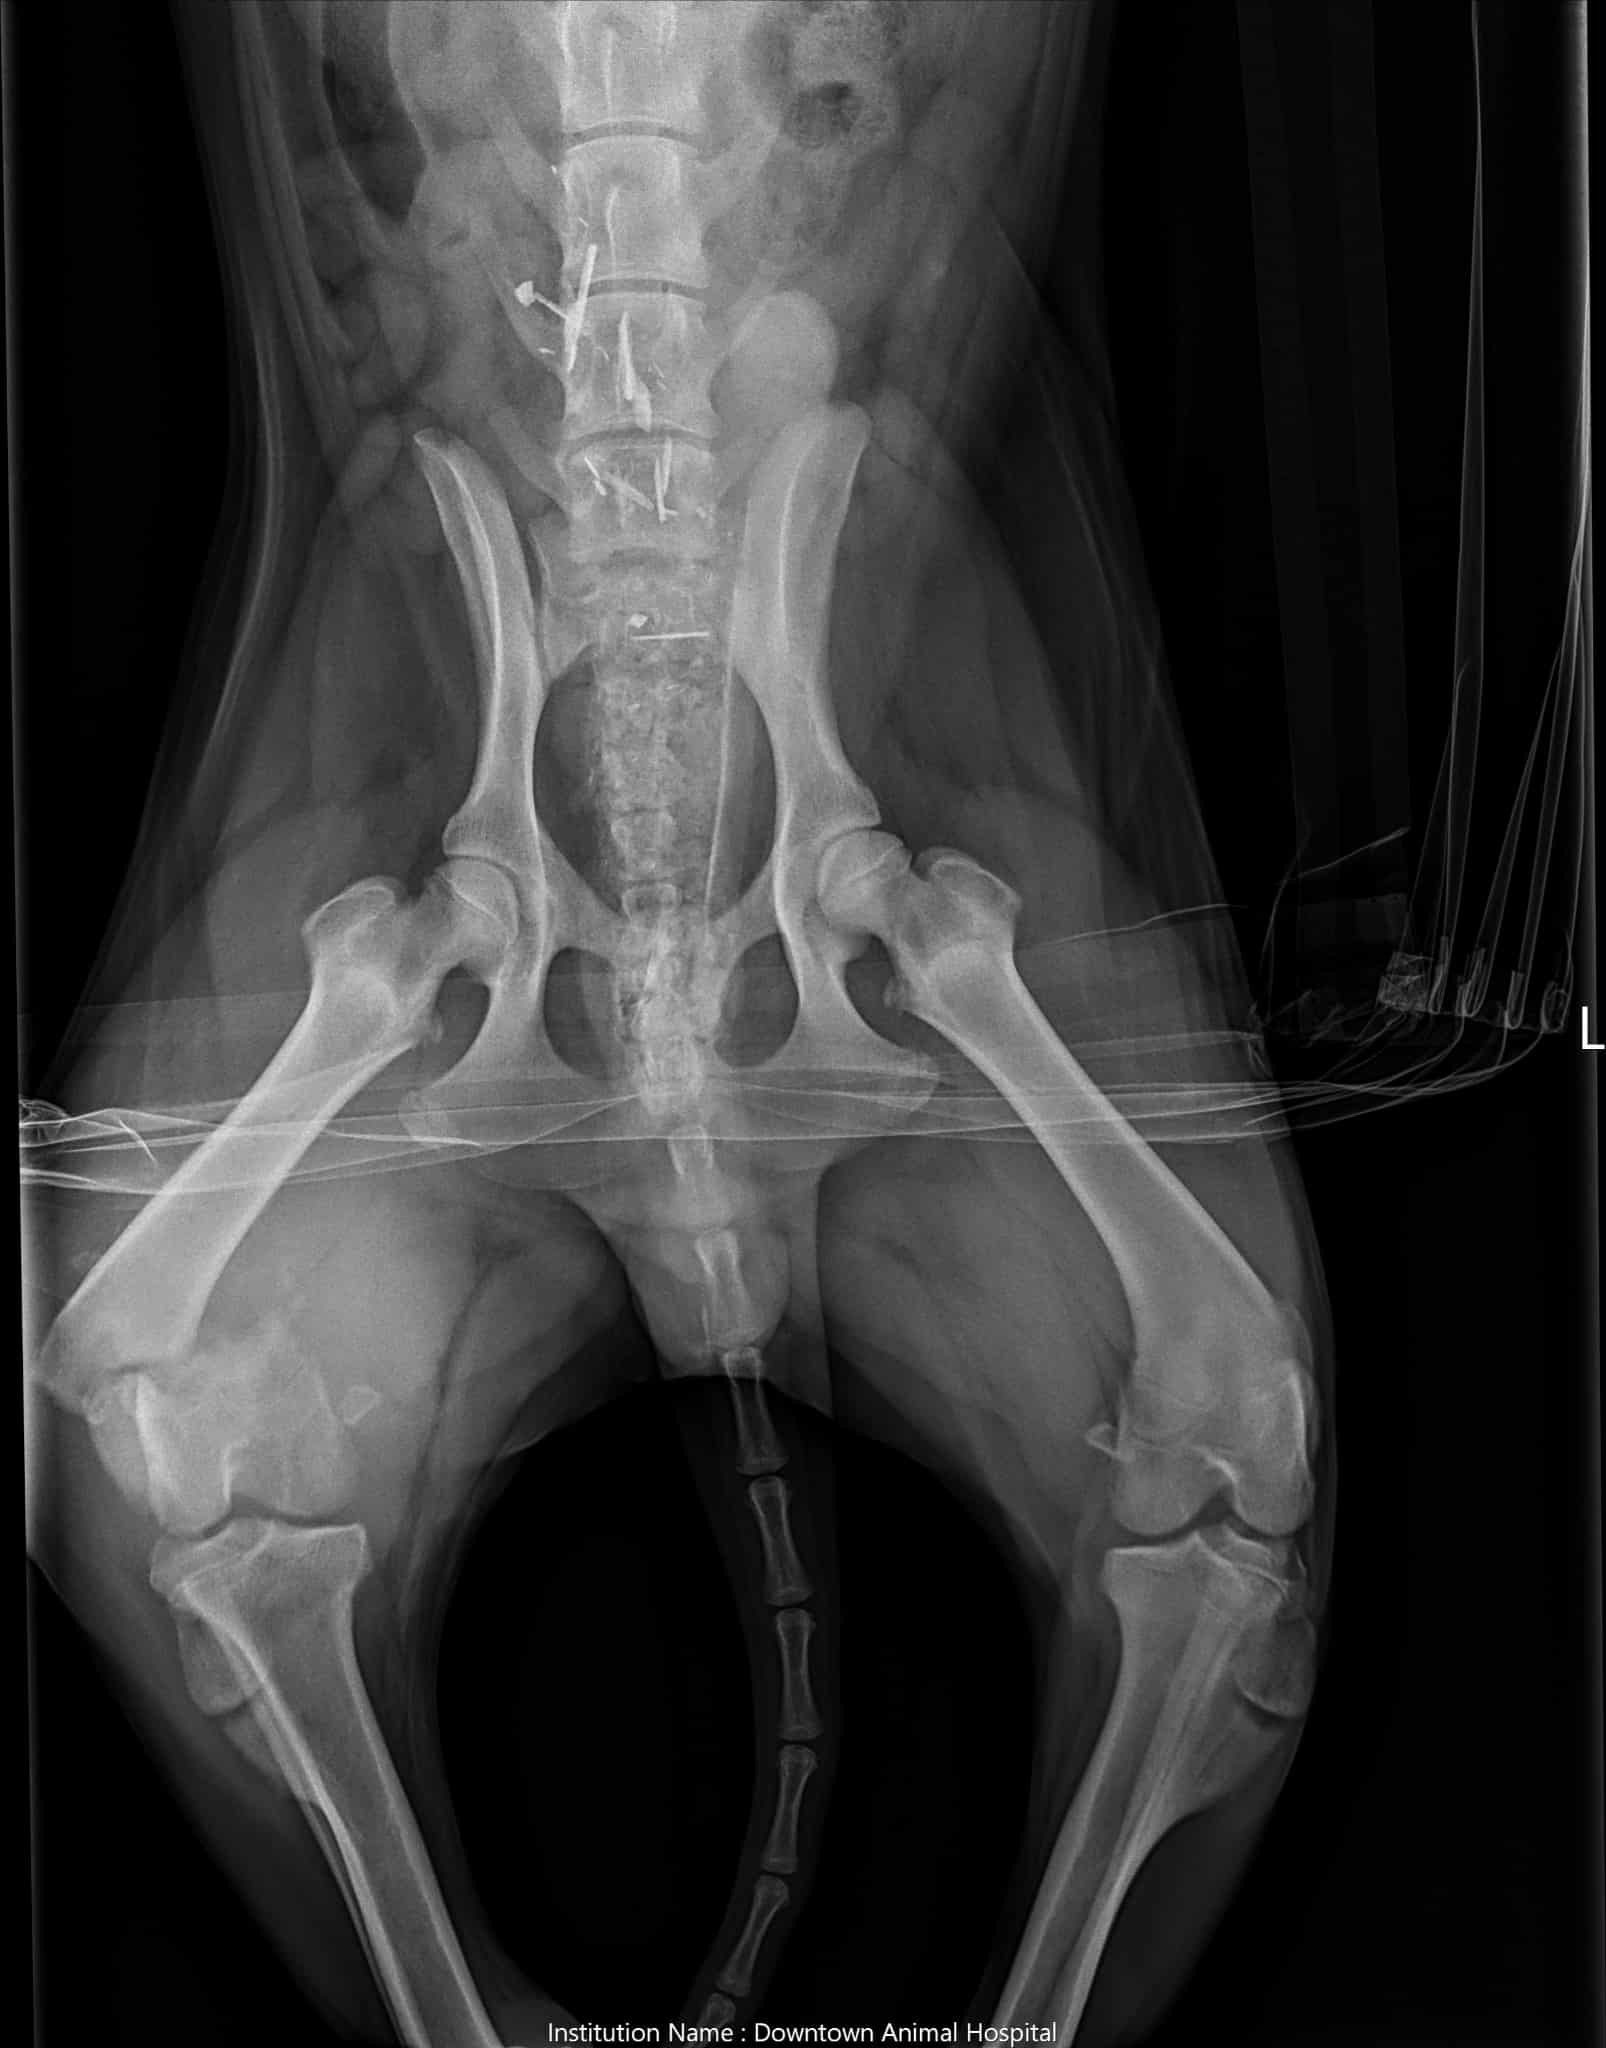

After numerous strokes left his father paralyzed Donald and his partner Missy needed to do major renovations on their home. Which was a huge financial burden that is still effecting them to this day. Their dog Joe is still just a puppy. But is currently in training to play a very important role in their lives. Donalds father has suffered over 2,000 strokes which can come on at any time. Missy, Joe's mom, also has epilepsy. He's not just a pet, he assists them in their daily lives. On Thursday an Amazon delivery driver who was unknown to them struck Joe. Thankfully no internal organs were damaged. Most of the injuries he suffered were to his leg. Joes tendons that are meant to hold his knee together are completely irreparable. The nerve endings have all been severed. His bones are broken and there's no blood flow. So it's basically dying from the knee down and needs to be removed. The estimated cost is approximately up to $7,000 or more, depending on factors that may come into play during the procedure. Amazon has been contacted. But unfortunately there were no other witnesses at the time of the incident. So the family has been left to cover the expenses. If you could please help by sharing this post or by donating anything you're able to. Joe is still young and deserves to walk and live a life without this damage. We really appreciate all the help we can get.